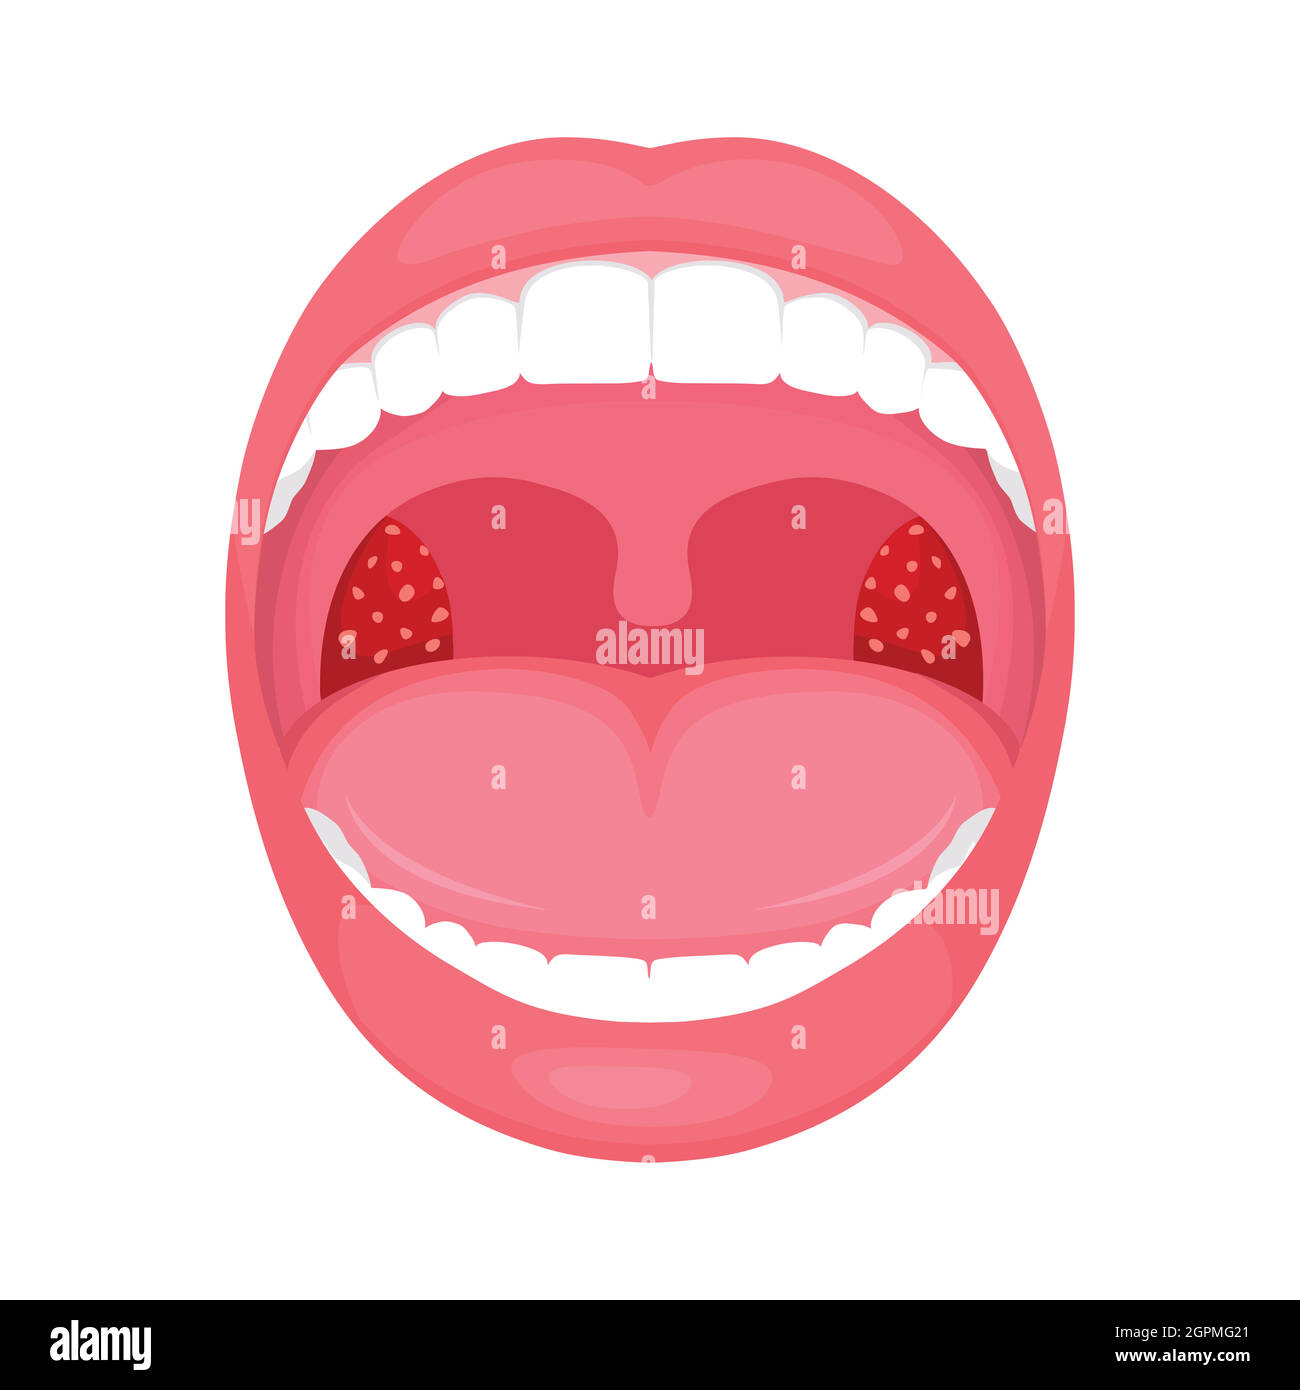

Illustration von weit geöffnetem Mund mit entzündeten Mandeln, Symptom der Tonsillitis Stockfotohttps://www.alamy.de/image-license-details/?v=1https://www.alamy.de/illustration-von-weit-geoffnetem-mund-mit-entzundeten-mandeln-symptom-der-tonsillitis-image361206881.html

Illustration von weit geöffnetem Mund mit entzündeten Mandeln, Symptom der Tonsillitis Stockfotohttps://www.alamy.de/image-license-details/?v=1https://www.alamy.de/illustration-von-weit-geoffnetem-mund-mit-entzundeten-mandeln-symptom-der-tonsillitis-image361206881.htmlRF2BYJB1N–Illustration von weit geöffnetem Mund mit entzündeten Mandeln, Symptom der Tonsillitis

Kehle bakterielle und virale Infektion, Mandeln Entzündung. Stock Vektorhttps://www.alamy.de/image-license-details/?v=1https://www.alamy.de/kehle-bakterielle-und-virale-infektion-mandeln-entzundung-image444233273.html

Kehle bakterielle und virale Infektion, Mandeln Entzündung. Stock Vektorhttps://www.alamy.de/image-license-details/?v=1https://www.alamy.de/kehle-bakterielle-und-virale-infektion-mandeln-entzundung-image444233273.htmlRF2GPMG21–Kehle bakterielle und virale Infektion, Mandeln Entzündung.